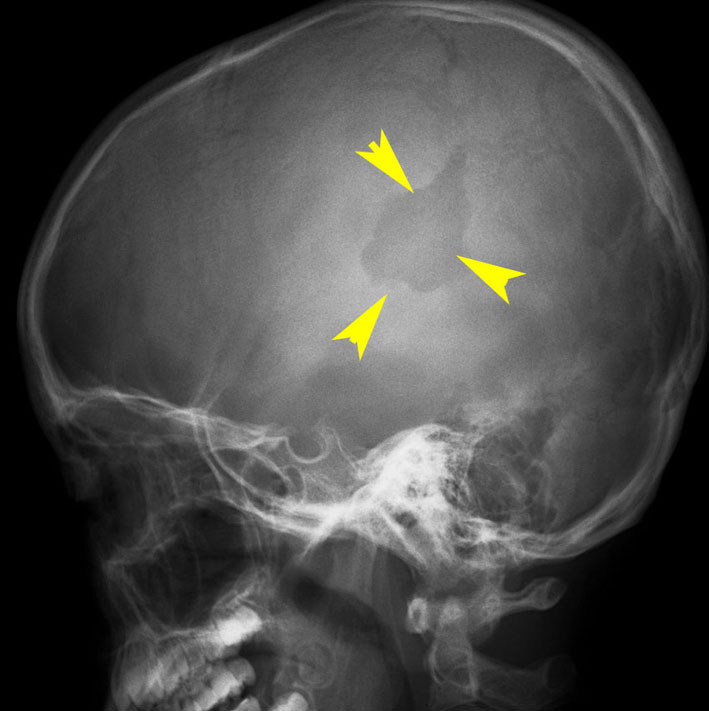

- レントゲン検査で,頭蓋骨が丸くポコンと抜けるように溶けているのが特長です

CTで典型的な頭蓋骨の打ち抜き像 punched out lesion が左頭頂骨にあります。これだけでLCHと診断がつくような画像です。

頭蓋骨のLCH

- 上の写真は,子供の右の頭頂骨にできたLCHで,頭部病変では最も多く見られるタイプです

- 頭蓋骨が丸く抜けるように破壊されるのでpunched out lesionと表現されます